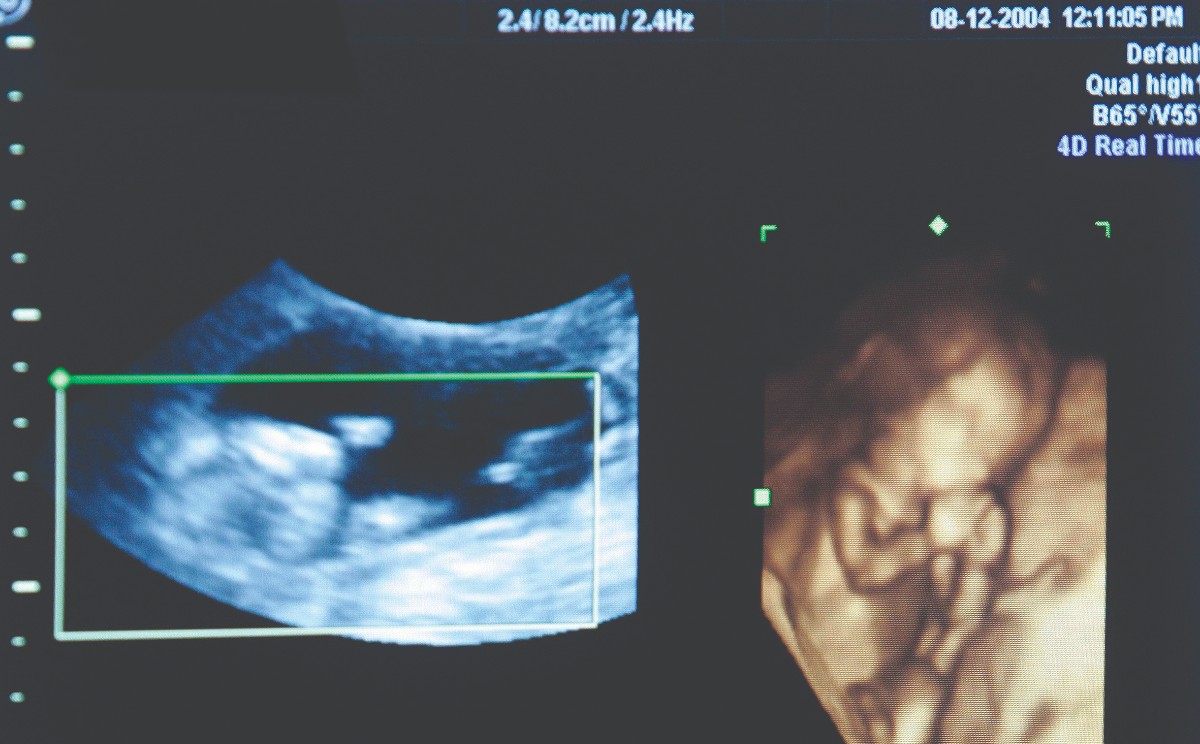

El especialista refirió que en esta clínica se ofrece un tratamiento integral, que comienza con un cita de evaluación, se realiza un ultrasonido pélvico a la mujeres, para observar su útero y sus ovarios, mientras que a los hombres se les hace un examen de espermatobioscopía.

Una vez que se avanza se elige el mejor método para la pareja, ya sean coitos programados, inseminación artificial o fertilización in vitro.